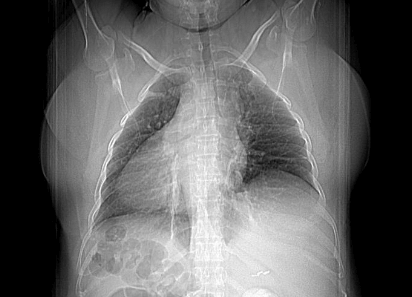

A chest X-ray revealed heart and stomach gas on the right side (Figure 1). A conventional transthoracic echocardiogram revealed dextrocardia without another abnormalities (Figure 2). A computerized tomography of the abdomen was performed and showed the liver on the left side, spleen and stomach on the right side. No other congenital malformations were found (Figure 3). Currently, the patient is 16 years old and under periodic systematic control at the Hematology and Cardiology services.

Figure 1: AP chest radiograph demonstrates dextrocardia. The cardiac apex and stomach gas are right-sided. The splenic shadow is in the right upper quadrant.